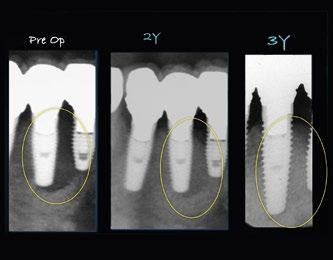

Klinisches Fallbeispiel

Die Röntgenaufnahme wies eine erheb iche Transparenz im Bereich des Implantats nahe Zahn 36 auf. Nach Entfernung der Suprakonstruktion konnten wir feststellen, dass das Implantat sich nicht gelockert hatte. Die Untersuchung ergab, dass sich dieser Fall der CIST-Klasse D zuordnen ließ.

Diese Röntgenaufnahmen wurden vor der Behandlung, 3 Monate nach und 2 Jahre nach der Behandlung erstellt. Das Implantat hat sich stabilisiert.

Die CT-Aufnahmen und die 3D-Darstellungen auf der Basis der CT-Daten zeigen, dass die Knochenbildung zufriedenstellend ist und das Implantat sich stabilisiert hat.